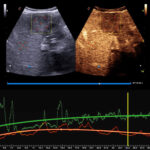

- XFlow technologijos pagalba gaunamas ypatingas tėkmės jautrumas ir aukšta rezoliucija. XFlow suteikia tiesioginį kraujo aido vizualizavimą.

- CnTI funkcijos pagalba pagerinamas vaizdo kontrastas

- microV funkcija, kuri skirta mikrokraujagyslių vizualizacijai